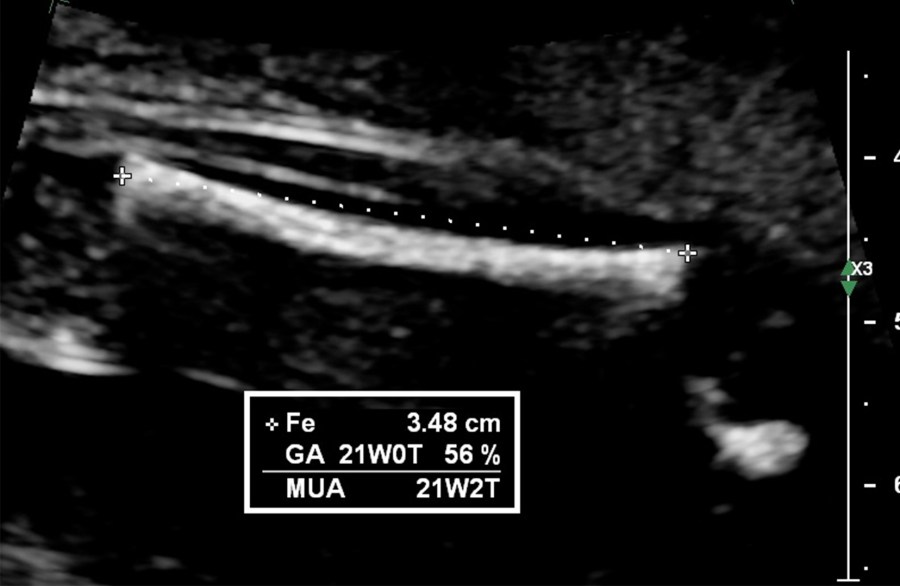

Measure the Fetal Femur

femur length ultrasound